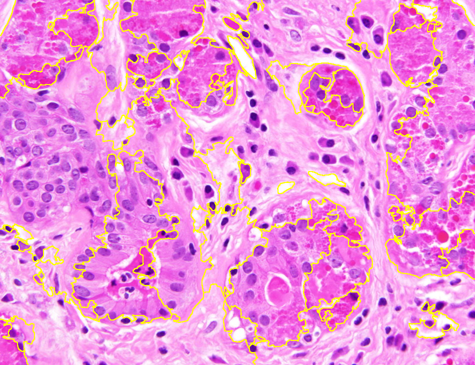

Dataset 3 consists of 50 annotated H&E-stained histological images from triple-negative breast cancer patients [74]. The images were acquired at 40× magnification using a Philips Ultra Fast Scanner (1.6RA) at the Curie Institute and contain a total of 4022 annotated cells.

Representative samples from the three datasets are shown in Fig. 1. In (a), the first frame of the synthetic video in Dataset 1 illustrates the strong illumination gradients produced by distance-dependent shading together with orientation-dependent interactions between vertex normals and the light direction. The H&E images in (b) and (c), also from Dataset 1, depict a mast cell infiltrate from a patient with non-alcoholic steatohepatitis and cirrhosis and, respectively, a sample from a patient with sclerosing polycystic adenosis of the parotid gland; the former consists primarily of purple nuclei, white cytoplasm, and pink extracellular tissue. Subfigures (d) and (e) show two examples from Dataset 2 accompanied by their ground-truth nuclei annotations, while (f) and (g) present a representative image from Dataset 3 together with its corresponding cell mask.

Figure 1: Samples from Datasets 1–3. (a) First frame of the 74-frame video in Dataset 1 (1770 × 880) with a superimposed red mesh. (b,c) H&E-stained tissue images from Dataset 1 (1000 × 750; 950 × 730). (d,e) Cell images from Dataset 2 (600 × 600) with nuclei annotations. (f,g) Image from Dataset 3 (512 × 512) with annotation.